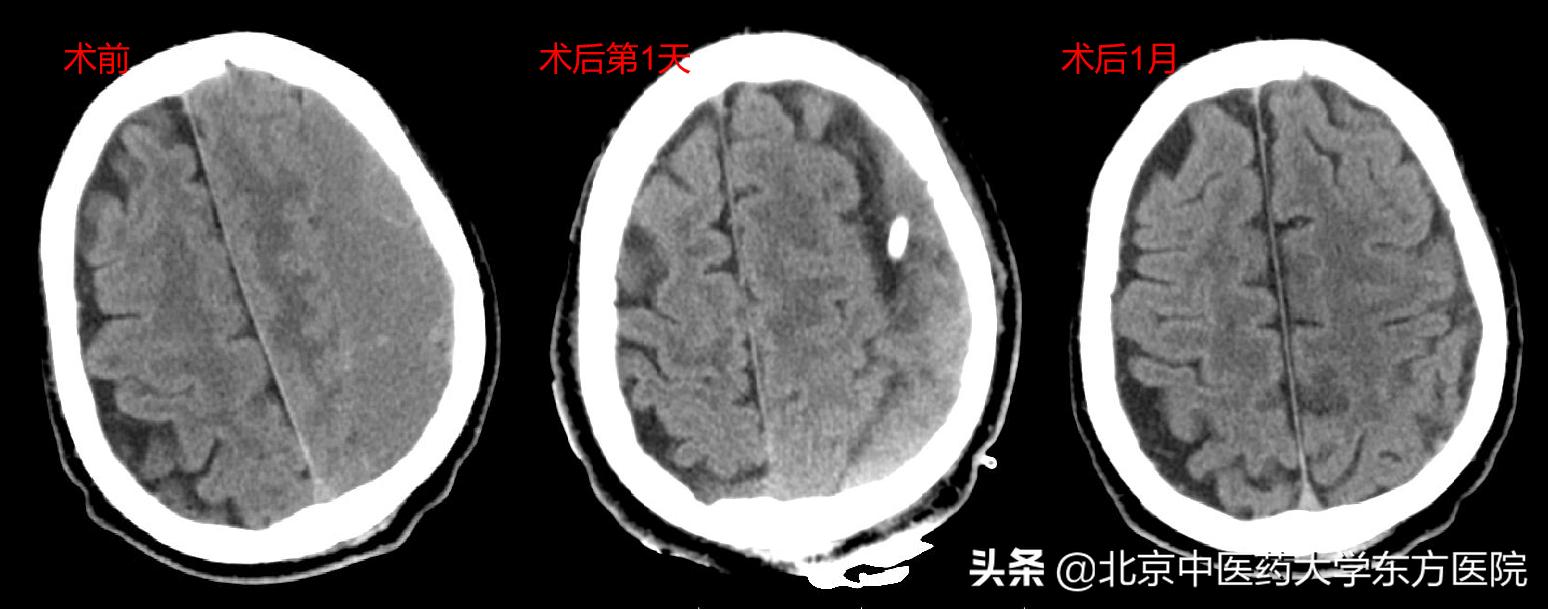

(2)手术治疗

① 钻孔/锥颅引流术(最常见)

6、慢性硬膜下血肿的预后如何?

慢性硬膜下血肿的预后比较好,一般不会留下后遗症,应早诊断、早治疗。术后有一定的复发率,应定期复查。